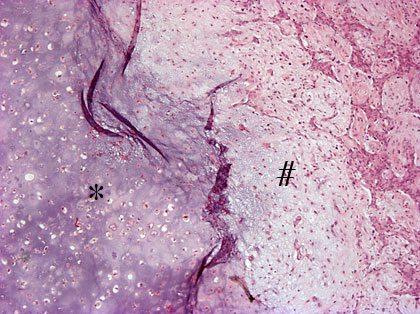

Pleomorfinen adenooma (adenoma pleomorphicum) 40x

Korvasylkirauhasen tuumorissa epiteliaalinen solukko muodostaa pieniä tiehyitä ja kystia. Stroomassa on tavallisesti sidekudoslima-aineita (#, "myxoid") ja rustometaplasiaa (*). 40x suurennos, HE-värjäys.